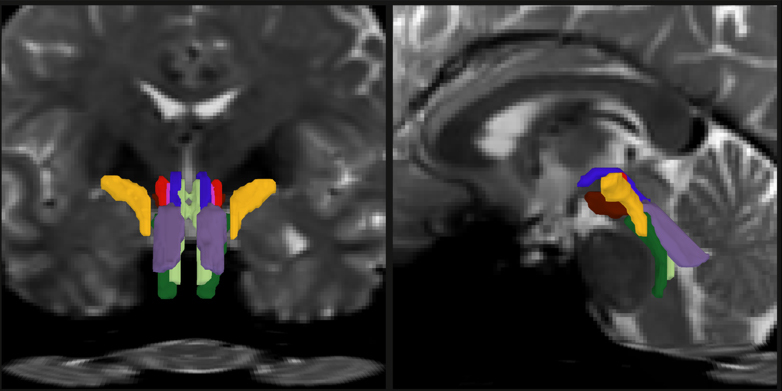

Nghiên cứu công bố ngày 6/2 trên tạp chí Proceedings of the National Academy of Sciences (PNAS) giới thiệu phần mềm BrainStem Bundle Tool (BSBT), cho phép tự động phân đoạn tám bó sợi trắng riêng biệt trong ảnh cộng hưởng từ khuếch tán (diffusion MRI) ở người sống. Công cụ này đã phát hiện những thay đổi cấu trúc đặc trưng ở bệnh nhân Parkinson, đa xơ cứng (MS), chấn thương sọ não (TBI) và cung cấp thêm dữ liệu liên quan đến Alzheimer. Đặc biệt, BSBT còn cho phép theo dõi quá trình hồi phục của một bệnh nhân hôn mê kéo dài bảy tháng.

BSBT được thiết kế để vượt qua rào cản này. Thuật toán trước tiên dựng bản đồ xác suất các bó sợi đi từ những vùng não lân cận như đồi thị và tiểu não xuống thân não. Sau đó, một mạng nơ-ron tích chập (convolutional neural network) tích hợp bản đồ này với nhiều lớp dữ liệu hình ảnh khác để phân biệt tám bó sợi riêng biệt.

Sau giai đoạn huấn luyện, BSBT có thể tự động xác định tám bó sợi trong các bộ dữ liệu mới. Khi thử nghiệm trên 40 tình nguyện viên được chụp hai lần cách nhau hai tháng, công cụ này liên tục xác định chính xác cùng một hệ bó sợi ở mỗi cá nhân. Nhóm nghiên cứu cũng kiểm tra chéo trên nhiều bộ dữ liệu độc lập và đánh giá riêng từng thành phần của mạng nơ-ron để bảo đảm độ tin cậy.